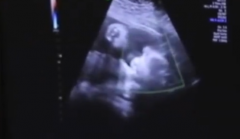

• 神奇!新生儿出生后右手食指现创口,原来竟是自己在妈妈肚子里嘬破的,3天

食指 男宝 水疱 2024/07/23

• 哭笑不得!新生儿在妈妈肚子里将手指嘬破

水泡 食指 子宫 2024/07/26